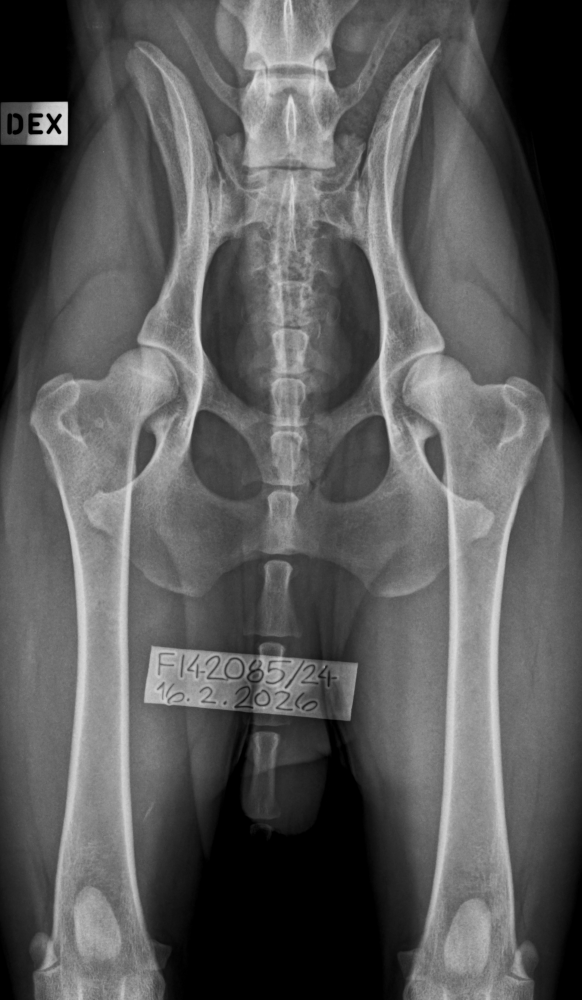

Terveystuloksia: JMVA Silent North Hope for the Future aka Kassu Lonkat B/B, kyynärät 0/0. Kassu on myös geneettisesti PraRdc4 sekä CCA puhdas 💚💚💚